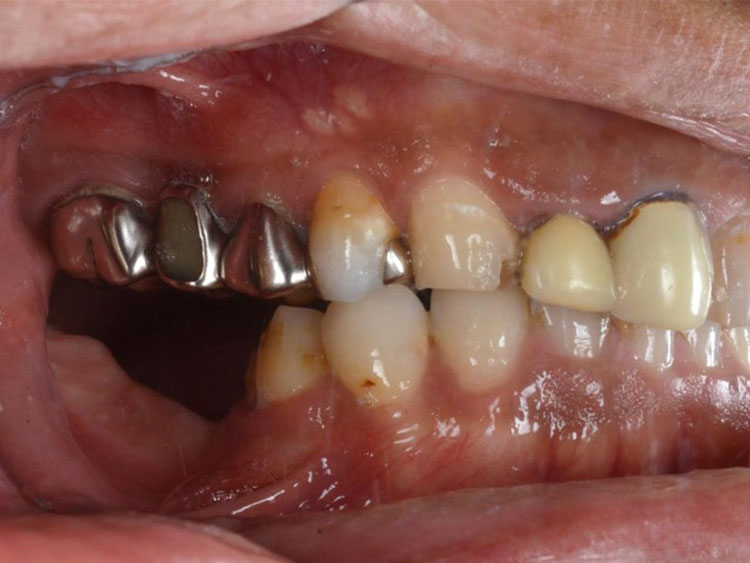

All-on-4症例 Case2

Treatment cases

Before

After